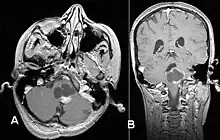

Pilocytic astrocytoma (and its variant pilomyxoid astrocytoma) is a brain tumor that occurs most commonly in children and young adults (in the first 20 years of life). They usually arise in the cerebellum, near the brainstem, in the hypothalamic region, or the optic chiasm, but they may occur in any area where astrocytes are present, including the cerebral hemispheres and the spinal cord. These tumors are usually slow growing and benign, corresponding to WHO malignancy grade 1.[1]

Usually – depending on the interview of the patient and after a clinical exam which includes a neurological exam and an ophthalmological exam – a CT scan and/or an MRI scan will be performed to confirm the presence of a tumor. They are usually easily distinguishable from normal brain structures using these imaging techniques. A special dye may be injected into a vein before these scans to provide contrast and make tumors easier to identify. Pilocytic astrocytomas are typically clearly visible on such scans, but it is often difficult to say based on imaging alone what type of tumor is present.

Pilocytic astrocytomas are often cystic tumors, and, if solid, tend to be well-circumscribed.

Under the microscope, the tumor is seen to be composed of bipolar cells with long "hair-like" GFAP-positive processes, giving the designation "pilocytic" (that is, made up of cells that look like fibers when viewed under a microscope[6]). Some pilocytic astrocytomas may be more fibrillary and dense in composition. The presence of Rosenthal fibers,[7] eosinophilic granular bodies, and microcysts can often be seen. Myxoid foci and oligodendroglioma-like cells may also be present, though these are not specific to pilocytic astrocytoma. Long-standing lesions may show hemosiderin-laden macrophages and calcifications.